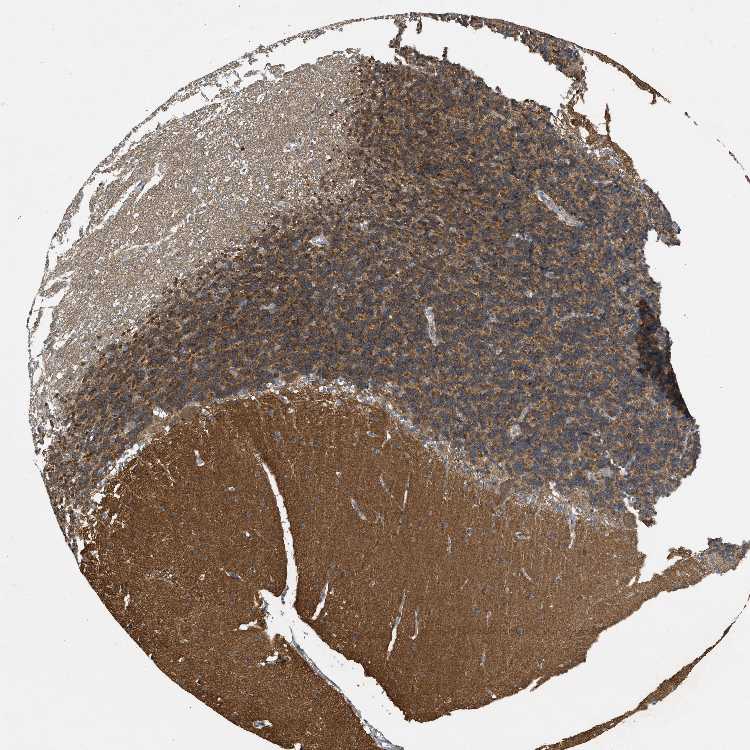

CEREBELLUM - Antibody stainingi

Antibody staining in the annotated cell types in the current human tissue is reported as not detected, low, medium, or high, based on conventional immunohistochemistry profiling in selected tissues. This score is based on the combination of the staining intensity and fraction of stained cells.

Each image is clickable and will lead to virtual microscopy that enables deeper exploration of all samples and also displays staining intensity scores, fraction scores and subcellular localization as well as patient and tissue information for each sample.

Antibody HPA012778Antibody CAB018581

Purkinje cells Medium-

Purkinje cells - cytoplasm/membrane -Low

Purkinje cells - dendrites -Not detected

Purkinje cells - nucleus -Not detected

Cells in granular layer Medium-

Cells in molecular layer Not detected-

Granular cells - cytoplasm/membrane -Medium

Granular cells - nucleus -Not detected

Molecular layer - neuropil -High

Molecular layer cells - cytoplasm/membrane -Not detected

Molecular layer cells - nucleus -Not detected

Processes in granular layer -Not detected

Processes in molecular layer -Not detected

Processes in white matter -Low

Synaptic glomeruli - capsule -Not detected

Synaptic glomeruli - core -High

White matter cells - cytoplasm/membrane -Not detected

White matter cells - nucleus -Not detected